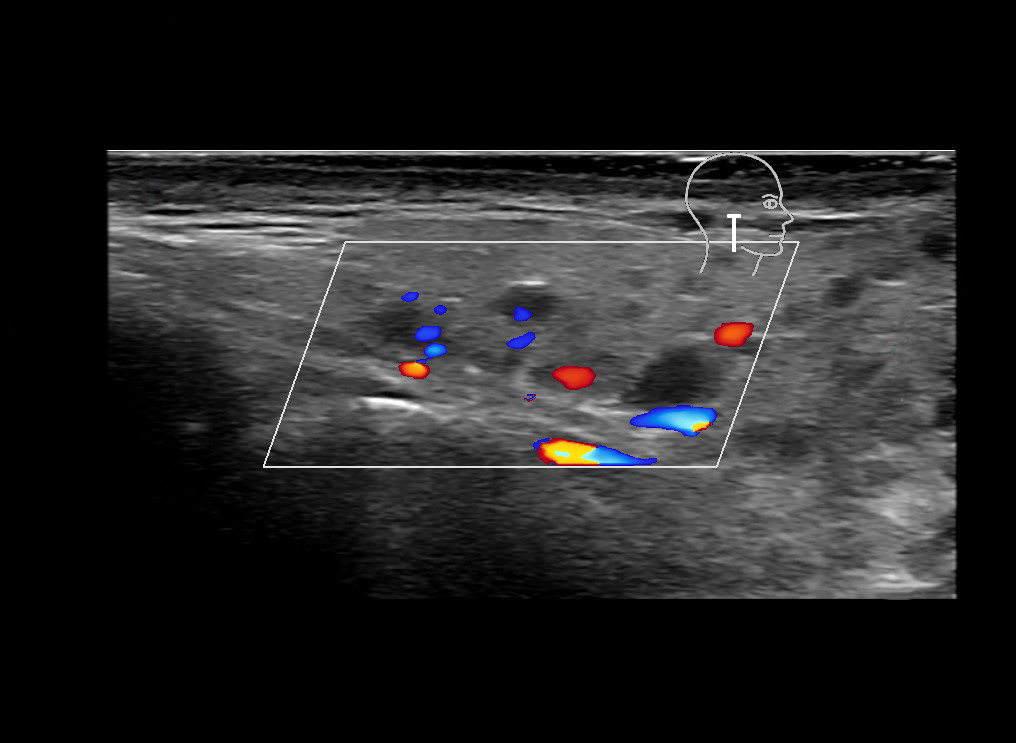

With ultrasound signs of inflammation can be visualized. Edema can be seen as a hyperechoic appearance of the subcutaneous fat, sometimes separated by hypoechoic fluid filled area’s, known as cobblestone appearance. Increased vascularization (hypervascularity) can be seen on colour Doppler. An abscess will appear as a fluid collection appearing as an irregular hypoechoic area with heterogeneous internal echoes and a thickened wall. Posterior acoustic enhancement can be present, and there is vascularity around but not within the mass. Under ultrasound guidance, abscesses can be managed by needle aspirations (18G) under antibiotic cover.